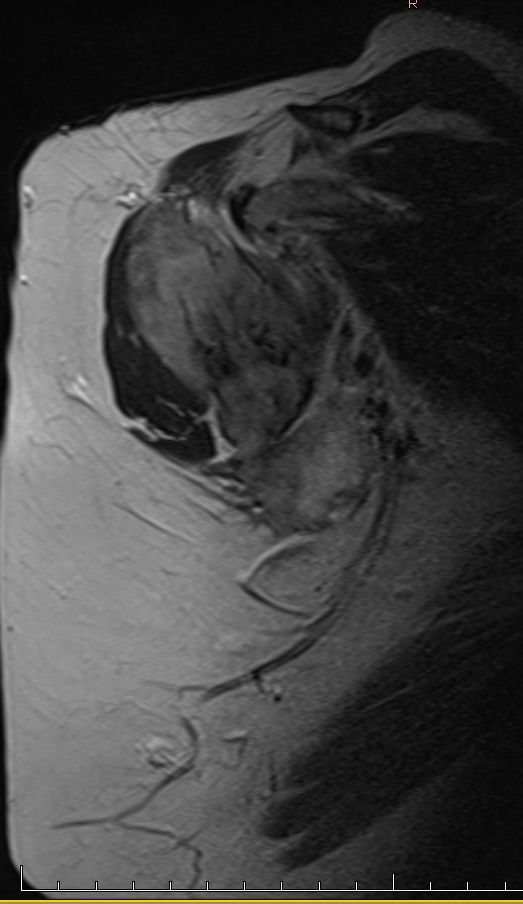

| Diagnostik | 56-jährige Frau mit einer derben, wenig verschieblichen Tumorbildung untergalb der linken Clavikula. ![]() |